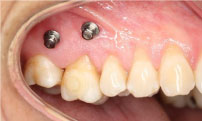

In six months tooth 1.6 was correctly positioned on the occlusal plane and the lower implant was in optimal condition to be rehabilitated. The crown was set on tooth 4.6 and the upper metallic retention and the micro screws were removed.

The stability of the treatment was accomplished by having both areas working together, implantology and rehabilitation. The intrusion of tooth 1.6 and the implant replacing tooth 4.6 will allow for the treatment to last in time, preventing any new changes in position (Figure 4).

Figure 4: Treatment finished. View Figure 4